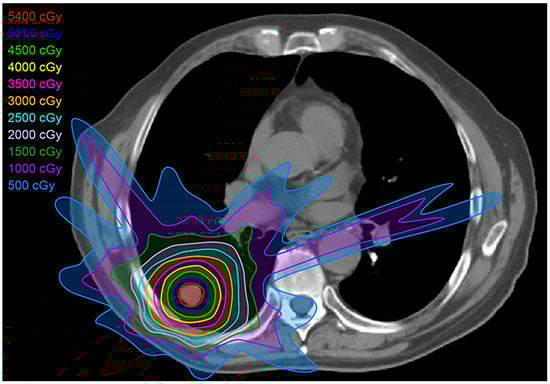

2.2. Three-Dimensional Conformal Radiotherapy

2.3. Intensity-Modulated Radiotherapy